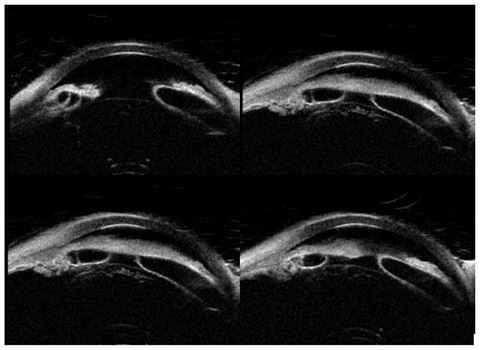

Images are Not Display Check it

Figure 2: UBM image sections of iris cyst in a 70-year-old male.

Accurate differentiation between iris cysts and iris melanoma is essential due to their vastly different clinical implications and management pathways. Iris cysts are typically benign, fluid-filled, and may be congenital or acquired due to trauma or inflammation. They usually appear translucent on slit-lamp examination and are best characterized using imaging modalities such as Ultrasound Biomicroscopy (UBM) and Anterior Segment Optical Coherence Tomography (AS-OCT) [1-3]. In contrast, iris melanoma arises from melanocytes and typically presents as a solid, pigmented lesion with irregular borders, intrinsic vascularity, and potential for local invasion and metastasis (Table 1). Diagnostic imaging and fluorescein angiography assist in assessing vascular characteristics and internal reflectivity. Unlike cysts, melanomas often display tortuous, leaky vessels and require more aggressive management, including excisional biopsy, plaque brachytherapy, or enucleation in advanced stages [4-7].